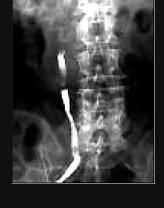

为了解肾损伤的部位、程度,哪项检查不适宜 ( )A、肾动脉造影B、B超肾脏C、双肾CTD、逆行肾盂造影E、排泄性尿路造影

问题 为了解肾损伤的部位、程度,哪项检查不适宜 ( )

选项 A、肾动脉造影 B、B超肾脏 C、双肾CT D、逆行肾盂造影 E、排泄性尿路造影

答案 D